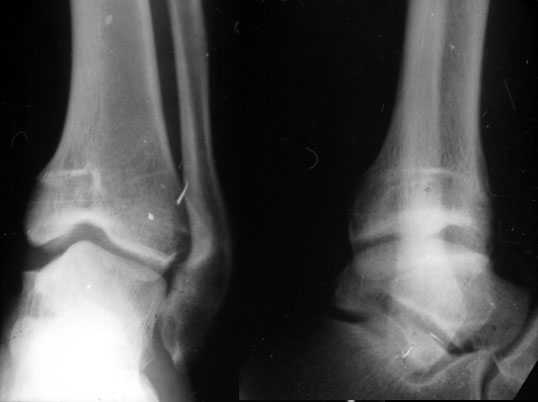

Аппаратом можно сделать все минимально инвазивно и травматично, вырастить клиновидный регенерат после чрескожной остеотомии через один или два разреза 0,5 см. В приложении похожий по локализации случай, только более давние последствия травмы с замыканием части зоны роста, деформация побольше, плюс укорочение голени было.

Померять однозначно сложно. Зато операция с аппаратом проще и быстрее. Провел-собрал-через прокол рубанул-1 шов-иди отдыхай. А открыто - и клиновидный дефект одномоментно может получиться большой, и очень короткий дистальный отломок фиксировать не очень будет удобно, потом на итоговых снимках вдруг обнаружится, что уголок не совсем такой, как планировали... Про другие возможные проблемы вспомнить можно...

Есть возможность аппаратом все исправить, а потом перейти на внутреннюю фиксацию.